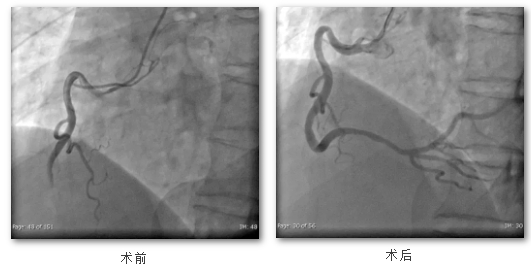

与此同时,心血管内科副主任涂焰明带领介入团队立即启动“心梗救治”绿色通道,无缝衔接至导管室进行急诊造影,造影结果显示右冠状动脉闭塞。经过紧张有序的抢救,心内介入团队历时60分钟顺利开通闭塞的血管,成功将患者从生死一线拉了回来。患者生命体征恢复平稳,胸闷胸痛症状消失。